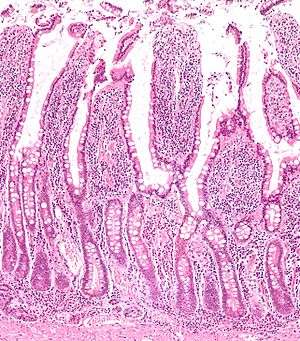

Micrograph of the small intestine mucosa showing the intestinal glands - bottom 1/3 of image. H&E stain. | |

In histology, an intestinal gland (also crypt of Lieberkühn and intestinal crypt) is a gland found in the intestinal epithelium lining of the small intestine and large intestine (colon). The glands and intestinal villi are covered by epithelium which contains multiple types of cells: enterocytes (absorbing water and electrolytes), goblet cells (secreting mucus), enteroendocrine cells (secreting hormones), cup cells, tuft cells and, at the base of the gland, Paneth cells (secreting anti-microbial peptides) and stem cells. These cells are not all present in the colon.

Intestinal glands are found in the epithelia of the small intestine, namely the duodenum, jejunum and ileum and in the large intestine (colon) where they are sometimes called colonic crypts. Intestinal glands of the small intestine contain a base of replicating stem cells, Paneth cells of the innate immune system, and goblet cells, which produce mucus.[1] In the colon, crypts do not have Paneth cells.[2]